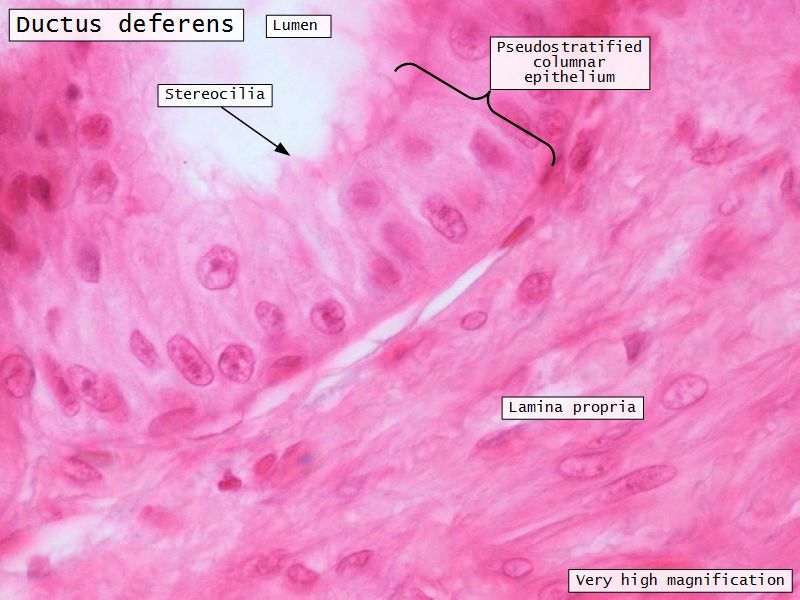

Ductus deferens

- Muscular duct with small lumen

- Lumen

- Pseudostratified columnar epithelium

- Stereocilia

- Fibroelastic lamina propria

Ductus deferens

- Longitudinal folds in

- Epithelium

- Lamina propria